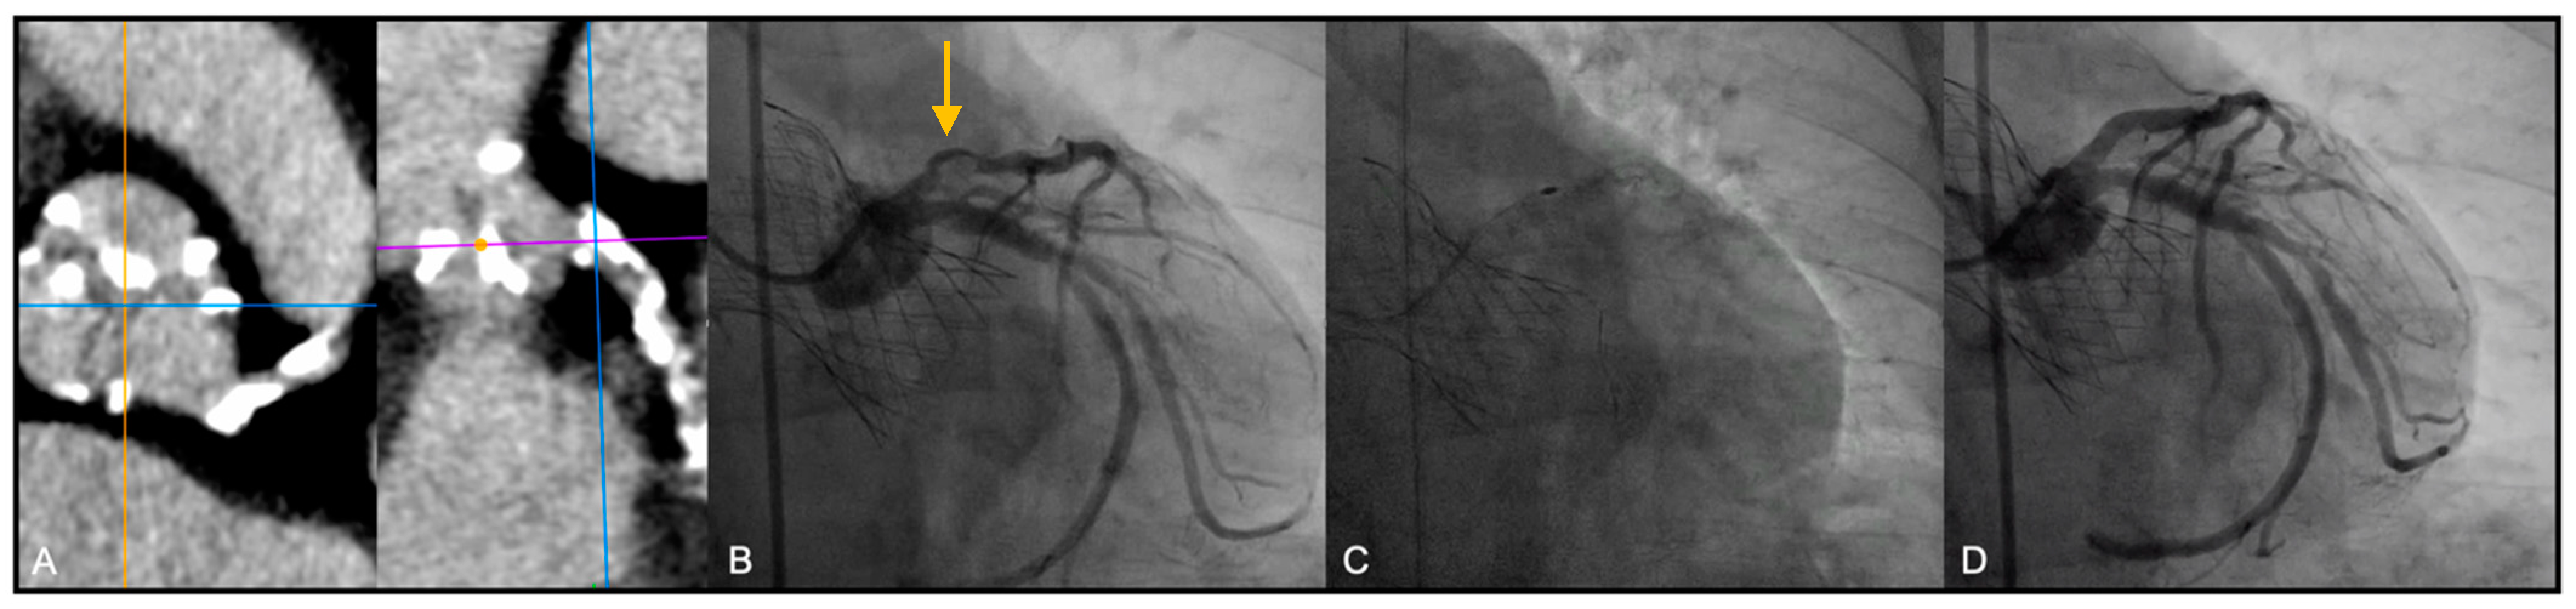

Most patients underwent TAVI via trans-femoral route (Figure 1). In 5 cases (26.3%) TAVI procedure was performed through a trans-apical access due to important vascular disease involving the ilio-femoral axis, not suitable for the trans-femoral TAVI delivery systems (Figure 2).

Figure 2. Rotational atherectomy (RA) following Edwards Sapien valve deployment by Trans-apical approach. (A) Balloon expandable valve (Edwards Sapien) deployment; (B) Pre RA angiographic evaluation of the lesion: severe calcified lesion of the ULM and ostial LAD (arrows); (C) Multiple Burr (RotaPro 1.5 mm) advancements; (D) Final result, after stent deployment and post dilation.